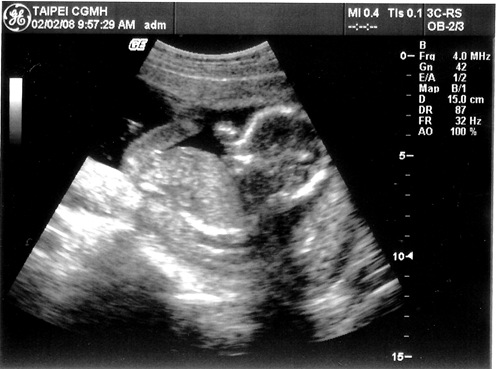

[產檢] 17週 寶寶頭大不是我的錯~~ ><

感覺有點擠~~

項  目 數 據 結 果 備 註

地點 02/02台北長庚 例行產檢

週數 17週

身長 15cm 體重約200g  ;  OK

心跳 150下/分鐘 OK

其他檢查 唐氏症抽血篩檢 預約高層次超音波

這星期主要還是看看超音波

量量寶寶的身長和估算體重有沒有在正常範圍

老婆邊照邊說寶寶頭很大..

沒想到醫生還跟著老婆瞎起鬨

說寶寶頭大像爸爸喔!!!   (明明寶寶頭的比例本來就比身體大得多...)   生氣...

這次照的超音波照也很清楚喔!!  真讚!!

寶寶還擺出鹹蛋超人的手交叉的動作..  五根手指己經看得清清楚楚了